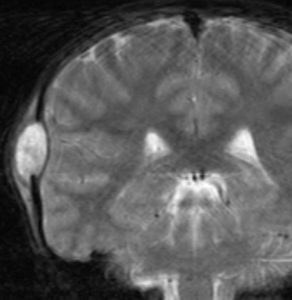

9歳の男の子です。右側頭部が腫れてきたのに気づきました。頭蓋骨のいびつな破壊像があります。

左はMRI T2強調画像です。まるで丸い腫瘍のように見えます。

下のT1強調画像では,ガドリニウム造影剤で強く増強されていて皮下に炎症性腫脹がみられ,活動期の病変であるのがわかります。

この病変は単発(孤発)病変ですが,ややいびつな形をしていて,頭皮の方に盛り上がっていますから,活動性の病変です。手術で完全摘出すると治りますから,骨欠損が広がるようなら手術したほうがいいです。理由は,手術が簡単なこと,病理診断がつくこと,これ以上の病変の広がりを抑えることです。最近は自然の骨に近いような人工骨で補填することができますが,骨形成しなくても自然修復で骨形成されます。とくに,低年齢児では骨形成をしない時もあります,頭蓋骨が自然再生するからです。